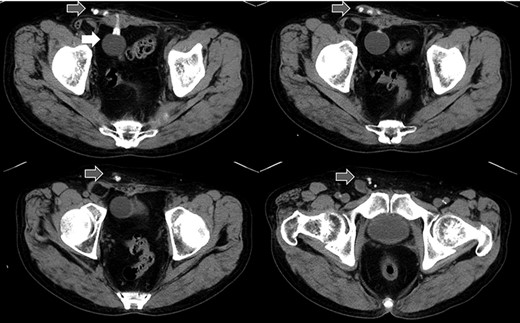

A 75-year-old male was referred for the treatment of a right IH. He also had received AUS implantation for a similar medical course. Abdominal CT demonstrated that a balloon was located beside the bladder and that the connecting catheter went through the rectus abdominis muscle and reached to the right scrotum through the subcutaneous layer (Fig. 5). The catheter was palpable subcutaneously; therefore, skin incision was placed on the outer site rather than in the normal situation. The diagnosis was indirect hernia and we did not observe any components of the AUS in the inguinal canal and repaired it using the Lichtenstein method.

Abdominal CT in Case 2: the balloon was located near the bladder and the tube went through rectus abdominis muscle; balloon, white arrow; tubes, gray arrows.